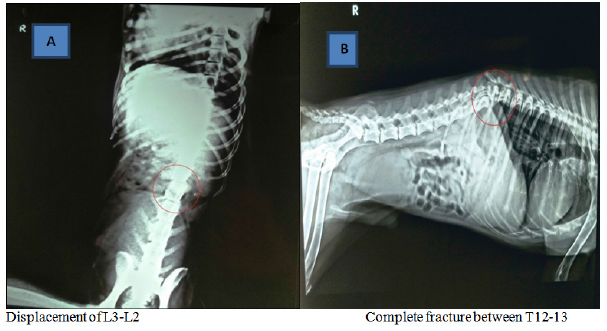

On survey radiography the patient were screened for the vertebral injuries as described in Table 1 and Figures 1A–1F, first case reflecting displacement of L3 in relation to L2, second case showed complete fracture between T12-13, third patient revealed compression in L3, fourth case had fracture of left pubic bone with compression of S3 and fifth and sixth case showed abnormality in both L1-2 and caudal 3 vertebrae. Plain radiography supports findings, formal interpretation for immobilizing the patient appropriately. The failure to adequately immobilize the spine owing to mechanism of injury diagnosis is a pitfall.9

Figure 1A–1F Radiographic investigations.